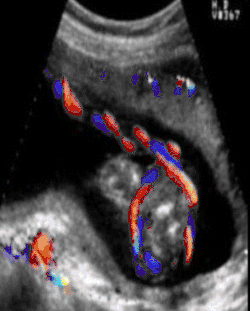

Ultrasound diagnosis of a cord around the neck was first described in 1982.[7] “Coils occur in about 25% of cases and ordinarily do no harm, but occasionally they may be so tight that constriction of the umbilical vessels and consequent hypoxia result.” Williams Obstetrics 16th Edition, has only one single sentence in the entire textbook regarding cords around the neck.[8] By contrast, the First Edition of the Encyclopædia Britannica from 1770 had 20 pages of information about Umbilical Cord Pathology with drawings of Umbilical Cord Entanglement. The Royal College of Obstetricians and Gynaecologists has these images on its brochure. There are currently three recent texts on ultrasonography which demonstrate the ability of ultrasound to identify umbilical cord issues with reliability as of 2009.

A study published in 2004 was done to establish the sensitivity of ultrasound in the diagnosis of a nuchal cord. Each of 289 women, induced the same day, underwent a transabdominal ultrasound scan with an Aloka 1700 ultrasound machine with a 3.5 MHz abdominal probe, using gray-scale and color Doppler imaging immediately prior to induction of labor. Presence of the cord was sought in the transverse and sagittal plane of the neck. A nuchal cord was diagnosed if the cord was visualized lying around at least 3 of the 4 sides of the neck. A cord was actually present at delivery in 52 of the 289 women. Only 18 of the 52 cords or 35% of the nuchal cords were detected on ultrasound done immediately before delivery, and 65% of nuchal cords were not detected. Of the 237 cases where there was no cord at delivery, ultrasound had false positive results, i.e. diagnosed a cord in 44 of the 237 cases (19%) in which there was no cord present at all. In this study, ultrasound was only 35% accurate at finding a single loop, and only 60% accurate at detecting a nuchal cord wrapped multiple times around the neck.[9]

In no study was it possible by ultrasound to distinguish between a loose or a tight cord, although at least 3 attempted to do so. Peregrine[9] concludes that ultrasound diagnosis of nuchal cords will only be useful if doctors are able to do so reliably and predict which of those fetuses are likely to have a problem. However, perinatologists routinely look for umbilical cord issues in monoamniotic twins. Studies have shown an improvement in outcomes where cord entanglement was prenatally identified in these cases. Ultrasound measurement of the velocity of flow in the cord may be useful in the management of twins and chronically growth-retarded fetuses. Of course this depends on the training of the sonographer. To date there are no ultrasound courses which teach the identification of nuchal cord to physicians or technicians. A recent review by Wilson of the American Academy of Ultrasonography Technicians recommends the documentation of umbilical cord issues.[10]